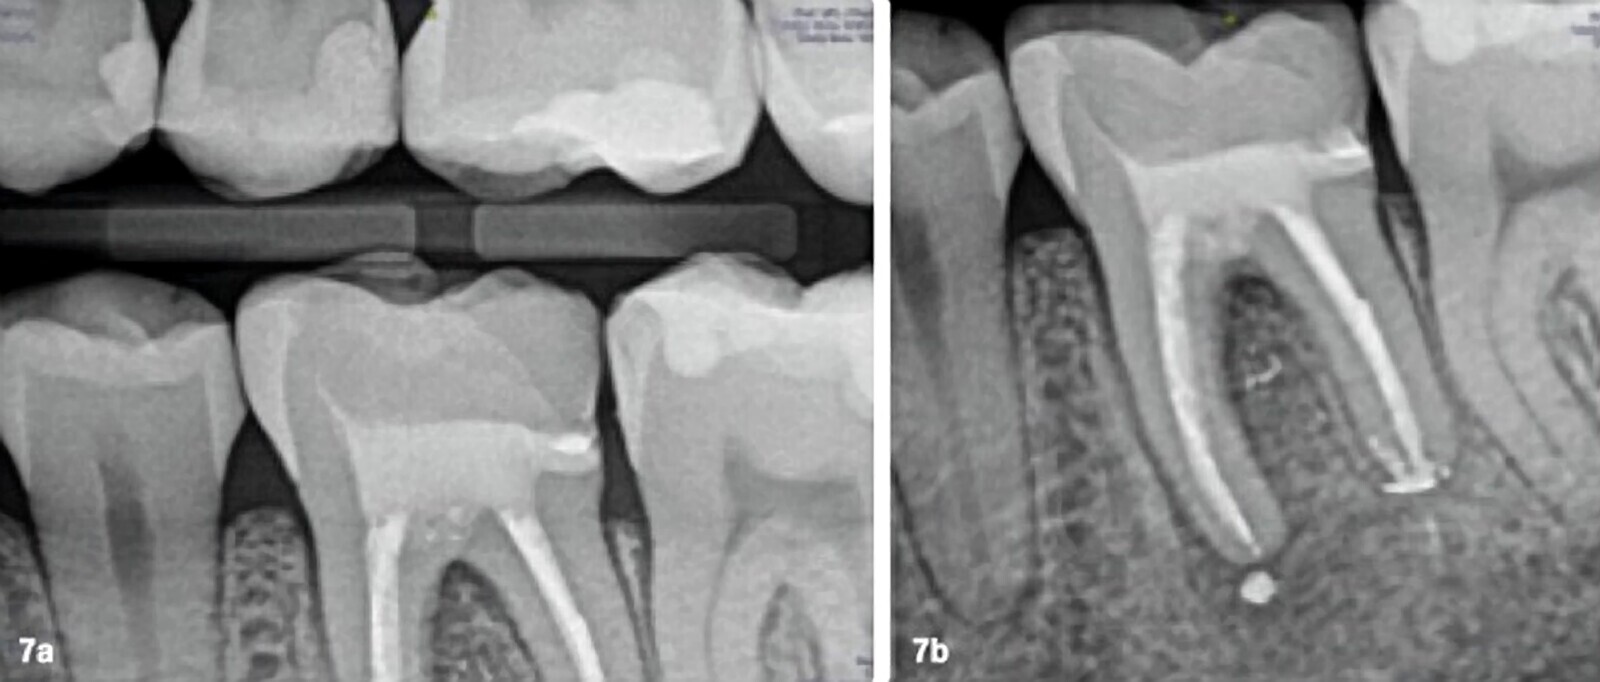

Figs. 7a y 7b. Radiografías finales del retratamiento no quirúrgico del 3.6. con su restauración indirecta cementada.